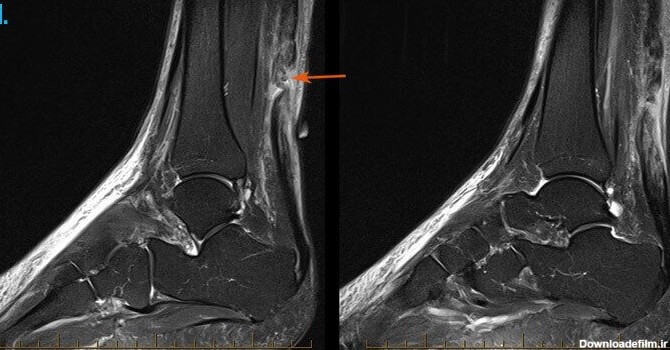

عکس ام ار ای پارگی رباط مچ پا

ام آر آی مچ پا یکی دیگر از اسکنهای شایع تصویربرداری پزشکی با ام آر آی است. در این اسکن به بررسی مچ پا ، پاشنه پا تاندون پا ، انگشتهای پا میپردازند.

پیچ خوردگی مچ پا و کشیدگی تاندون روی پا در آسیب های ورزشی جزو شایع ترین آسیب ها محسوب می شود. با توجه به اینکه این عارضه در اکثر ورزشکاران روی می دهد و می تواند عملکرد ورزشی را دچار اختلال نماید روش های درمانی موجود در کلینیک فیزیوتراپی مرکزی شریعتی برای درمان این گونه بیماران توصیه گردیده است.